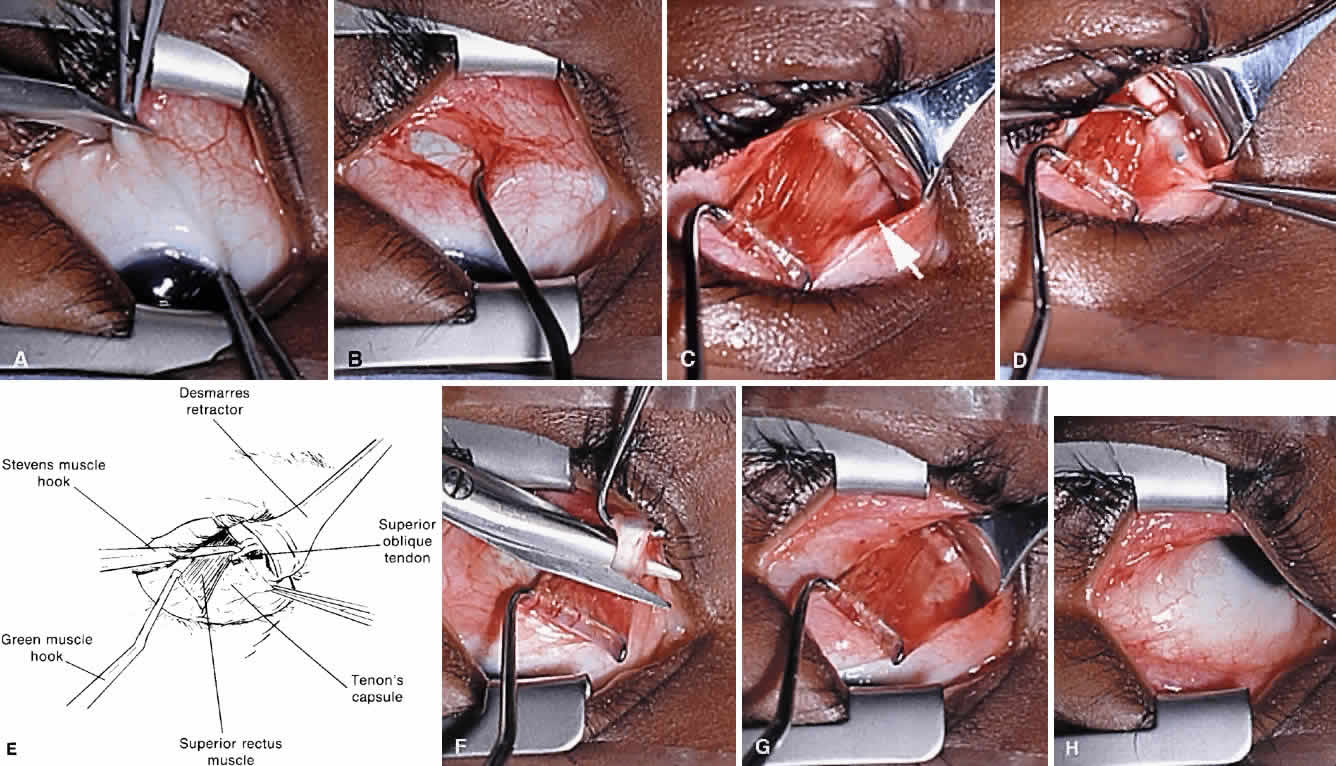

The Harada-Ito procedure is usually indicated in patients whose primary complaint is torsional diplopia (Fig. 2E, F and Fig. 8). This is encountered most often in adult patients with bilateral, posttraumatic superior oblique muscle palsy. Patients with congenital superior oblique palsy often have sensory adaptations that partially or completely compensate for years of excyclotropia. Although used primarily to correct symptomatic excyclotropia in patients with little or no vertical deviation in primary gaze position, it may also be effective in the treatment ocular torticollis with tilt-dependent nystagmus.52,53 The Harada-Ito procedure involves selective strengthening of the anterior fibers of the superior oblique tendon that are primarily responsible for incyclotorsion. It can be performed either by disinserting, advancing and anteriorly transposing the anterior tendon fibers (disinsertion technique) as described by Fells54 or by the classic Harada-Ito method, which redirects the anterior fibers as a “dog leg” without scleral disinsertion (Fig. 8).40 We prefer the classic method because it is more easily reversible. However, the disinsertion technique has the advantage of being readily modified for use with adjustable sutures.41,55 Superior oblique tendon tuck limited to the anterior fibers is an occasionally useful alternative when an intermediate amount of incycloduction is desired with some vertical correction.

To perform the classic Harata-Ito procedure, the superior oblique tendon is identified and isolated on a muscle hook in a fashion similar to a superior oblique tendon tuck (see previous discussion). A small muscle hook is used to separate between one third and one quarter of the most anterior tendon fibers for approximately 8 to 10 mm from their scleral insertion. A nonabsorbable, double-armed suture, such as 5-0 braided Dacron, is passed through the tendon defect and then through the sclera adjacent to the superior border of the lateral rectus muscle posterior to its scleral insertion. When the suture is secured to the sclera, the anterior fibers are advanced and anteriorly transposed to create a new functional insertion. The surgical effect can be titrated by altering both the tension and position of the suture using an intraoperative adjustment technique in cooperative patients or fundus examination under general anesthesia.56 Postoperative overcorrection can easily be addressed by cutting the scleral suture. If performed during the first several days after surgery, the transposed fibers of superior oblique tendon return to their normal anatomic position.